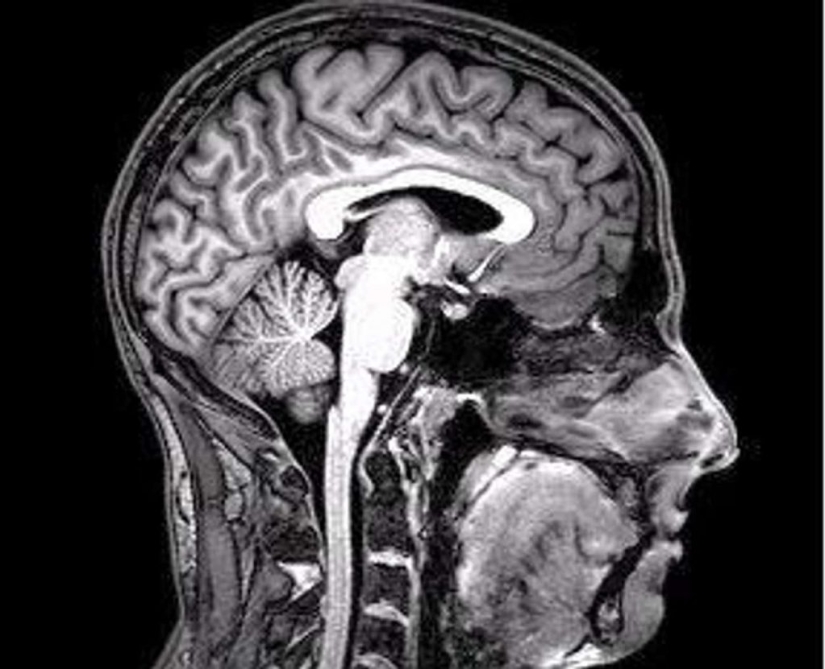

6. Although yawning has traditionally been considered a sign of sleepiness or boredom, evolutionary psychologist Andrew Gallup says, "Recent evidence suggests that yawning may help cool the brain." This "cooling" effect occurs when you take a deep breath, stretching your jaw to increase blood flow, causing a downward flow of cerebrospinal fluid and blood from the brain. This allows the incoming air to slightly cool down liquids. And why are we doing this at night? According to Gallup, “At night, when we are about to go to bed, our brain and body temperatures reach their highest point during the day.”